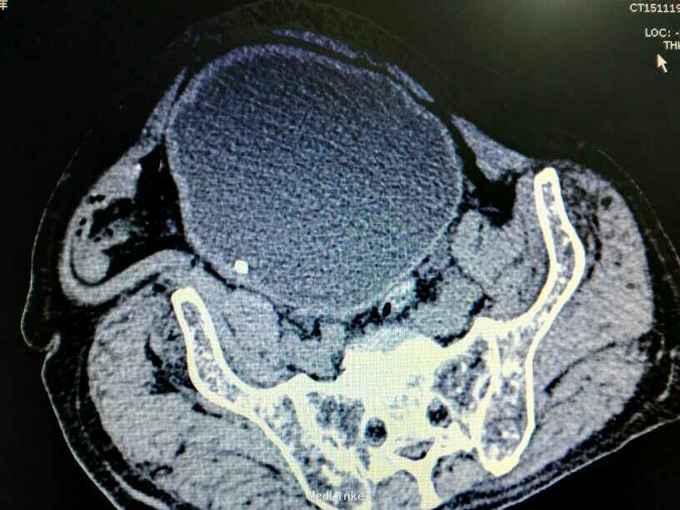

男性,87岁,进行性排尿困难10年,小便不能自解2天入院。无血尿,无发热、腰痛。一直口服藏药治疗前列腺增生症。既往无高血压、糖尿病。

腹部明显膨隆。耻骨上膀胱区扣浊。肾区无扣痛。尿常规少许白细胞。肌酐506,电解质正常。Hb116。

前列腺增生症 尿潴留 双肾积水 肾功能不全,膀胱结石,尿路感染,双肾多发囊肿。给予留置导尿,间断分次放尿后,出现肉眼血尿,持续膀胱冲洗,颜色较红,伴血凝块间断堵管。